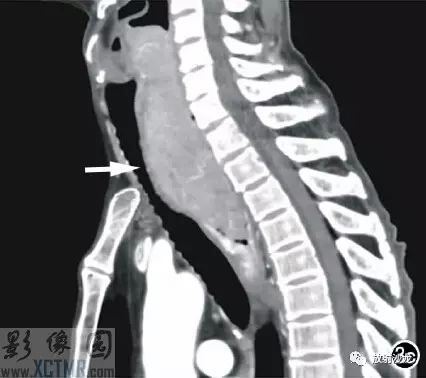

上消化道鋇餐:食管胸上段可見不規則充盈缺損,約5.6cm*4.2cm,黏膜結構紊亂,管壁不規整,對比劑通過稍緩慢,會厭動度不協調,考慮食管癌(圖2)。CT:食管胸上段見軟組織腫塊,上自杓會厭披裂,下至主動脈弓水平,腫塊邊緣清晰,密度均勻,增強掃描輕到中度不均勻強化,食管腔狹窄,氣管、右側甲狀腺、鄰近血管受壓移位(圖3),縱隔未見腫大淋巴結,診斷:食管癌可能。